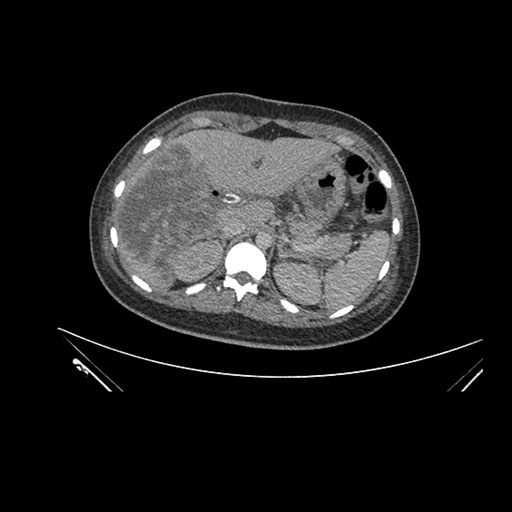

Axial Arterial

Axial Venous